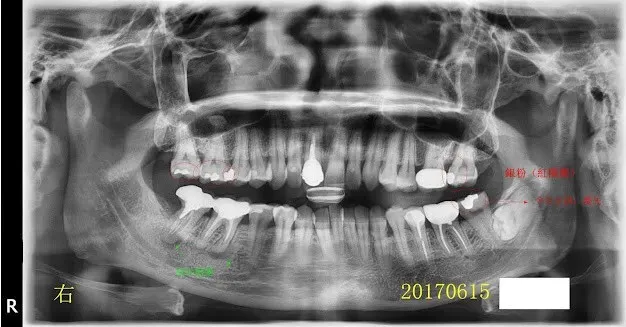

假牙材質11-根尖病變+除汞+智齒

我忘了這位病人後來是否有來做後續的治療,我猜應該是沒有,因為我沒印象。但我那時都已經幫他精心劃好治療計畫的圖(方便他理解龐大的工程,對,這就像預售屋之類的藍圖)。 就不浪費了,剛拿來紙上談兵,模擬計畫,what if一下。